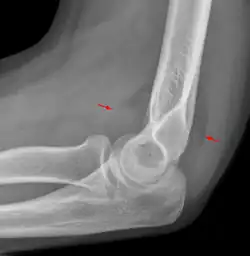

Fat pad sign

The fat pad sign, also known as the sail sign, is a potential finding on elbow radiography which suggests a fracture of one or more bones at the elbow. It may indicate an occult fracture that is not directly visible. Its name derives from the fact that it has the shape of a spinnaker (sail).[1] It is caused by displacement of the fat pad around the elbow joint. Both anterior and posterior fat pad signs exist, and both can be found on the same X-ray.

In children, a posterior fat pad sign suggests a condylar fracture of the humerus. In adults it suggests a radial head fracture.

The fat pad sign is invaluable in assessing for the presence of an intra-articular fracture of the elbow. An anterior fat pad is often normal. However a posterior fat pad seen on a lateral x-ray of the elbow is always abnormal. The patient will be unable to flex their elbow and requires orthopaedic input.[2]